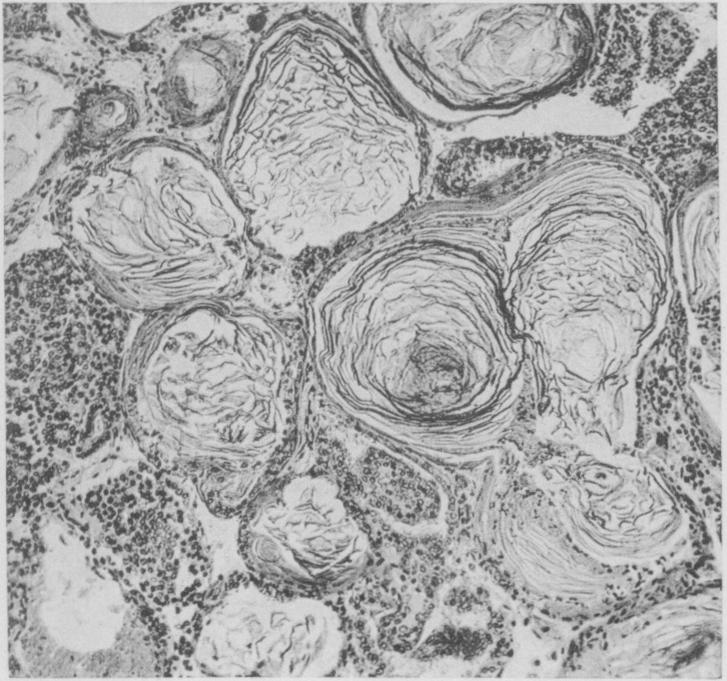

A Series of spontaneous tumors in Mice with Observations on the Influence of Heredity on the Frequency of their Occurrence.

J Med Res. 1909 Oct;21(3):479-518.13.

PMID:19971929

原文链接:https://pmc.ncbi.nlm.nih.gov/articles/PMC2099039/